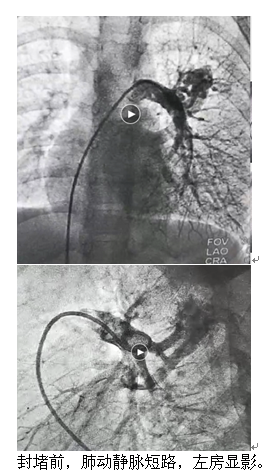

充分的完善術(shù)前準(zhǔn)備后,青島市婦女兒童醫(yī)院多學(xué)科聯(lián)合為夕夕完成了肺動(dòng)靜脈瘺介入栓塞封堵術(shù),手術(shù)過(guò)程非常順利,心導(dǎo)管造影檢查進(jìn)一步明確診斷后,在DSA引導(dǎo)下用可控彈簧圈成功封堵了肺動(dòng)靜脈瘺。